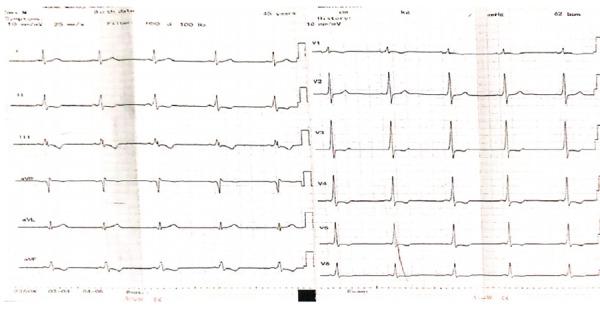

Wolff-Parkinson-White syndrome, an electrophysiological disorder of heart caused by preexcitation of an abnormal accessory pathway,can either be asymptomatic or may present with palpitation or exertional dyspnea. We report a case of an asymptomatic 45-year-old male with incidental finding of Wolff-Parkinson-White syndrome posted for laparoscopic cholecystectomy under general anesthesia. The anesthetic management of these patients is challenging as they are prone to develop life-threatening tachyarrhythmia. Taking all the necessary precautions to prevent tachyarrhythmia, balanced anesthesia, rigorous monitoring and preparedness with necessary drugs and equipment to treat any complications is the cornerstone for positive outcome. Keywords: accessory pathway; tachyarrhythmia; WPW syndrome.

沃-帕-怀综合征,一种由异常旁路预激引起的心脏电生理紊乱,可无症状,也可表现为心悸或运动性呼吸困难。我们报告了一例无症状的 45 岁男性,偶然发现沃-帕-怀综合征,在全身麻醉下接受腹腔镜胆囊切除术。这些患者的麻醉管理具有挑战性,因为他们容易发生危及生命的心动过速。采取一切必要的预防措施来预防心动过速,平衡麻醉,严格监测,并准备好必要的药物和设备来治疗任何并发症,是取得积极结果的基石。关键词:旁路;心动过速;WPW 综合征。